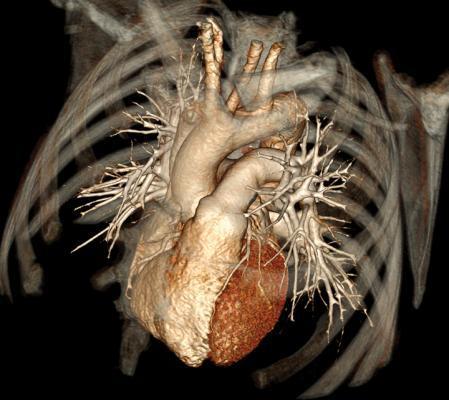

The data generated from these tests is presented numerically, using graphs or x-ray like images. RMHD moves beyond, numerical data / graphs and presents heart disease in a completely novel way. It will use the latest advancements in data visualization tools to create 3D graphic rich animations of the disease (eg. Computed Tomography Angiogram).

We can’t fix it, if we can’t see it.

By presenting the disease visually, we make it real. By aggregating the data over the course of a lifetime we will be able to visually milestone the disease from onset to reversal.